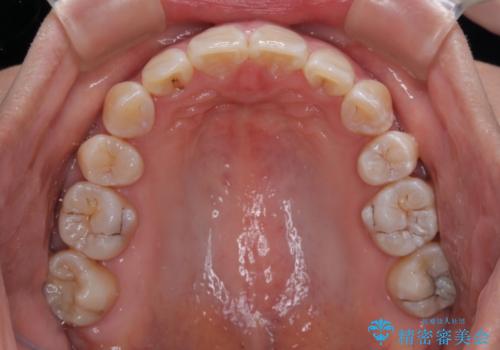

ご本人がびっくりするくらい劇的に口元の突出感が改善され、大変満足のいく仕上がりとなりました。

骨格的に上顎歯列が前方位にあり、口元の突出感が顕著な状態で、上下左右の第一小臼歯4本を抜歯して、ワイヤー装置での抜歯矯正を行うこととしました。

奥歯の咬み合わせ改善のために、アンカースクリューの使用と上顎左右第一小臼歯の抜歯のタイミングをコントロールして、理想的な咬み合わせに仕上げていくこととしました。